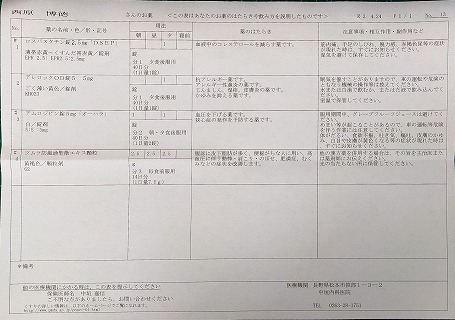

2021.11.13より 西原クリニック 0968-62-0622

2024.7.12(金) 2回目のコロナ感染 7.16(火)検査で陽性

2024.4.13 オロパタジンに戻る

2024.3.9 鼻炎と目のかゆみがひどく、オロパタジン⇒デザレックス&点眼薬 アレジオン に変更 2.10 血液検査結果

2023.11.13 ウイルス性の風邪と診断 熱の最大は13日夜 37.1℃

23.04.18 コロナ陽性

22.10.29 鼻炎薬吸引 モメタゾン点鼻液50μg 噴霧用 5mg10g 杏林 56噴霧用

22.09.10

2022.02.19

2021.12.04 西原クリニック処方箋=pdf

2021.11.13

2021.04.24 2021.03.06 中垣医院処方箋 =PDF